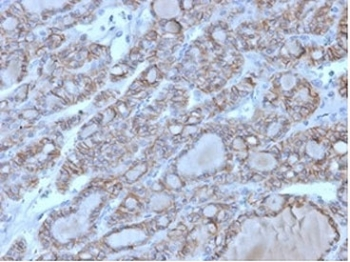

| Description | Mouse monoclonal antibody to CD56 (NCAM1) |

| Tested applications | IHC, WB |

| Dilution range | WB 1:2000, IHC 1:150 |

| Target | CD56 |